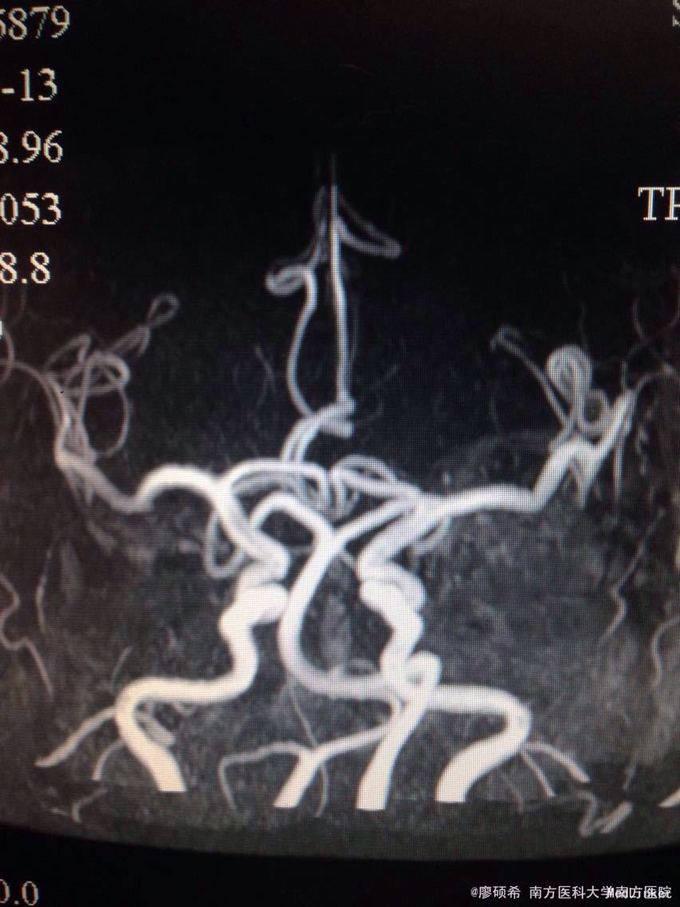

查体未见明显阳性体征。 颅脑MR示脑动脉硬化

基底动脉延长扩张症。予改善循环,营养神经等治疗。

患者颅脑MR影像科未报基底动脉延长扩张,上级医师自阅片子后决定给她下这个诊断。